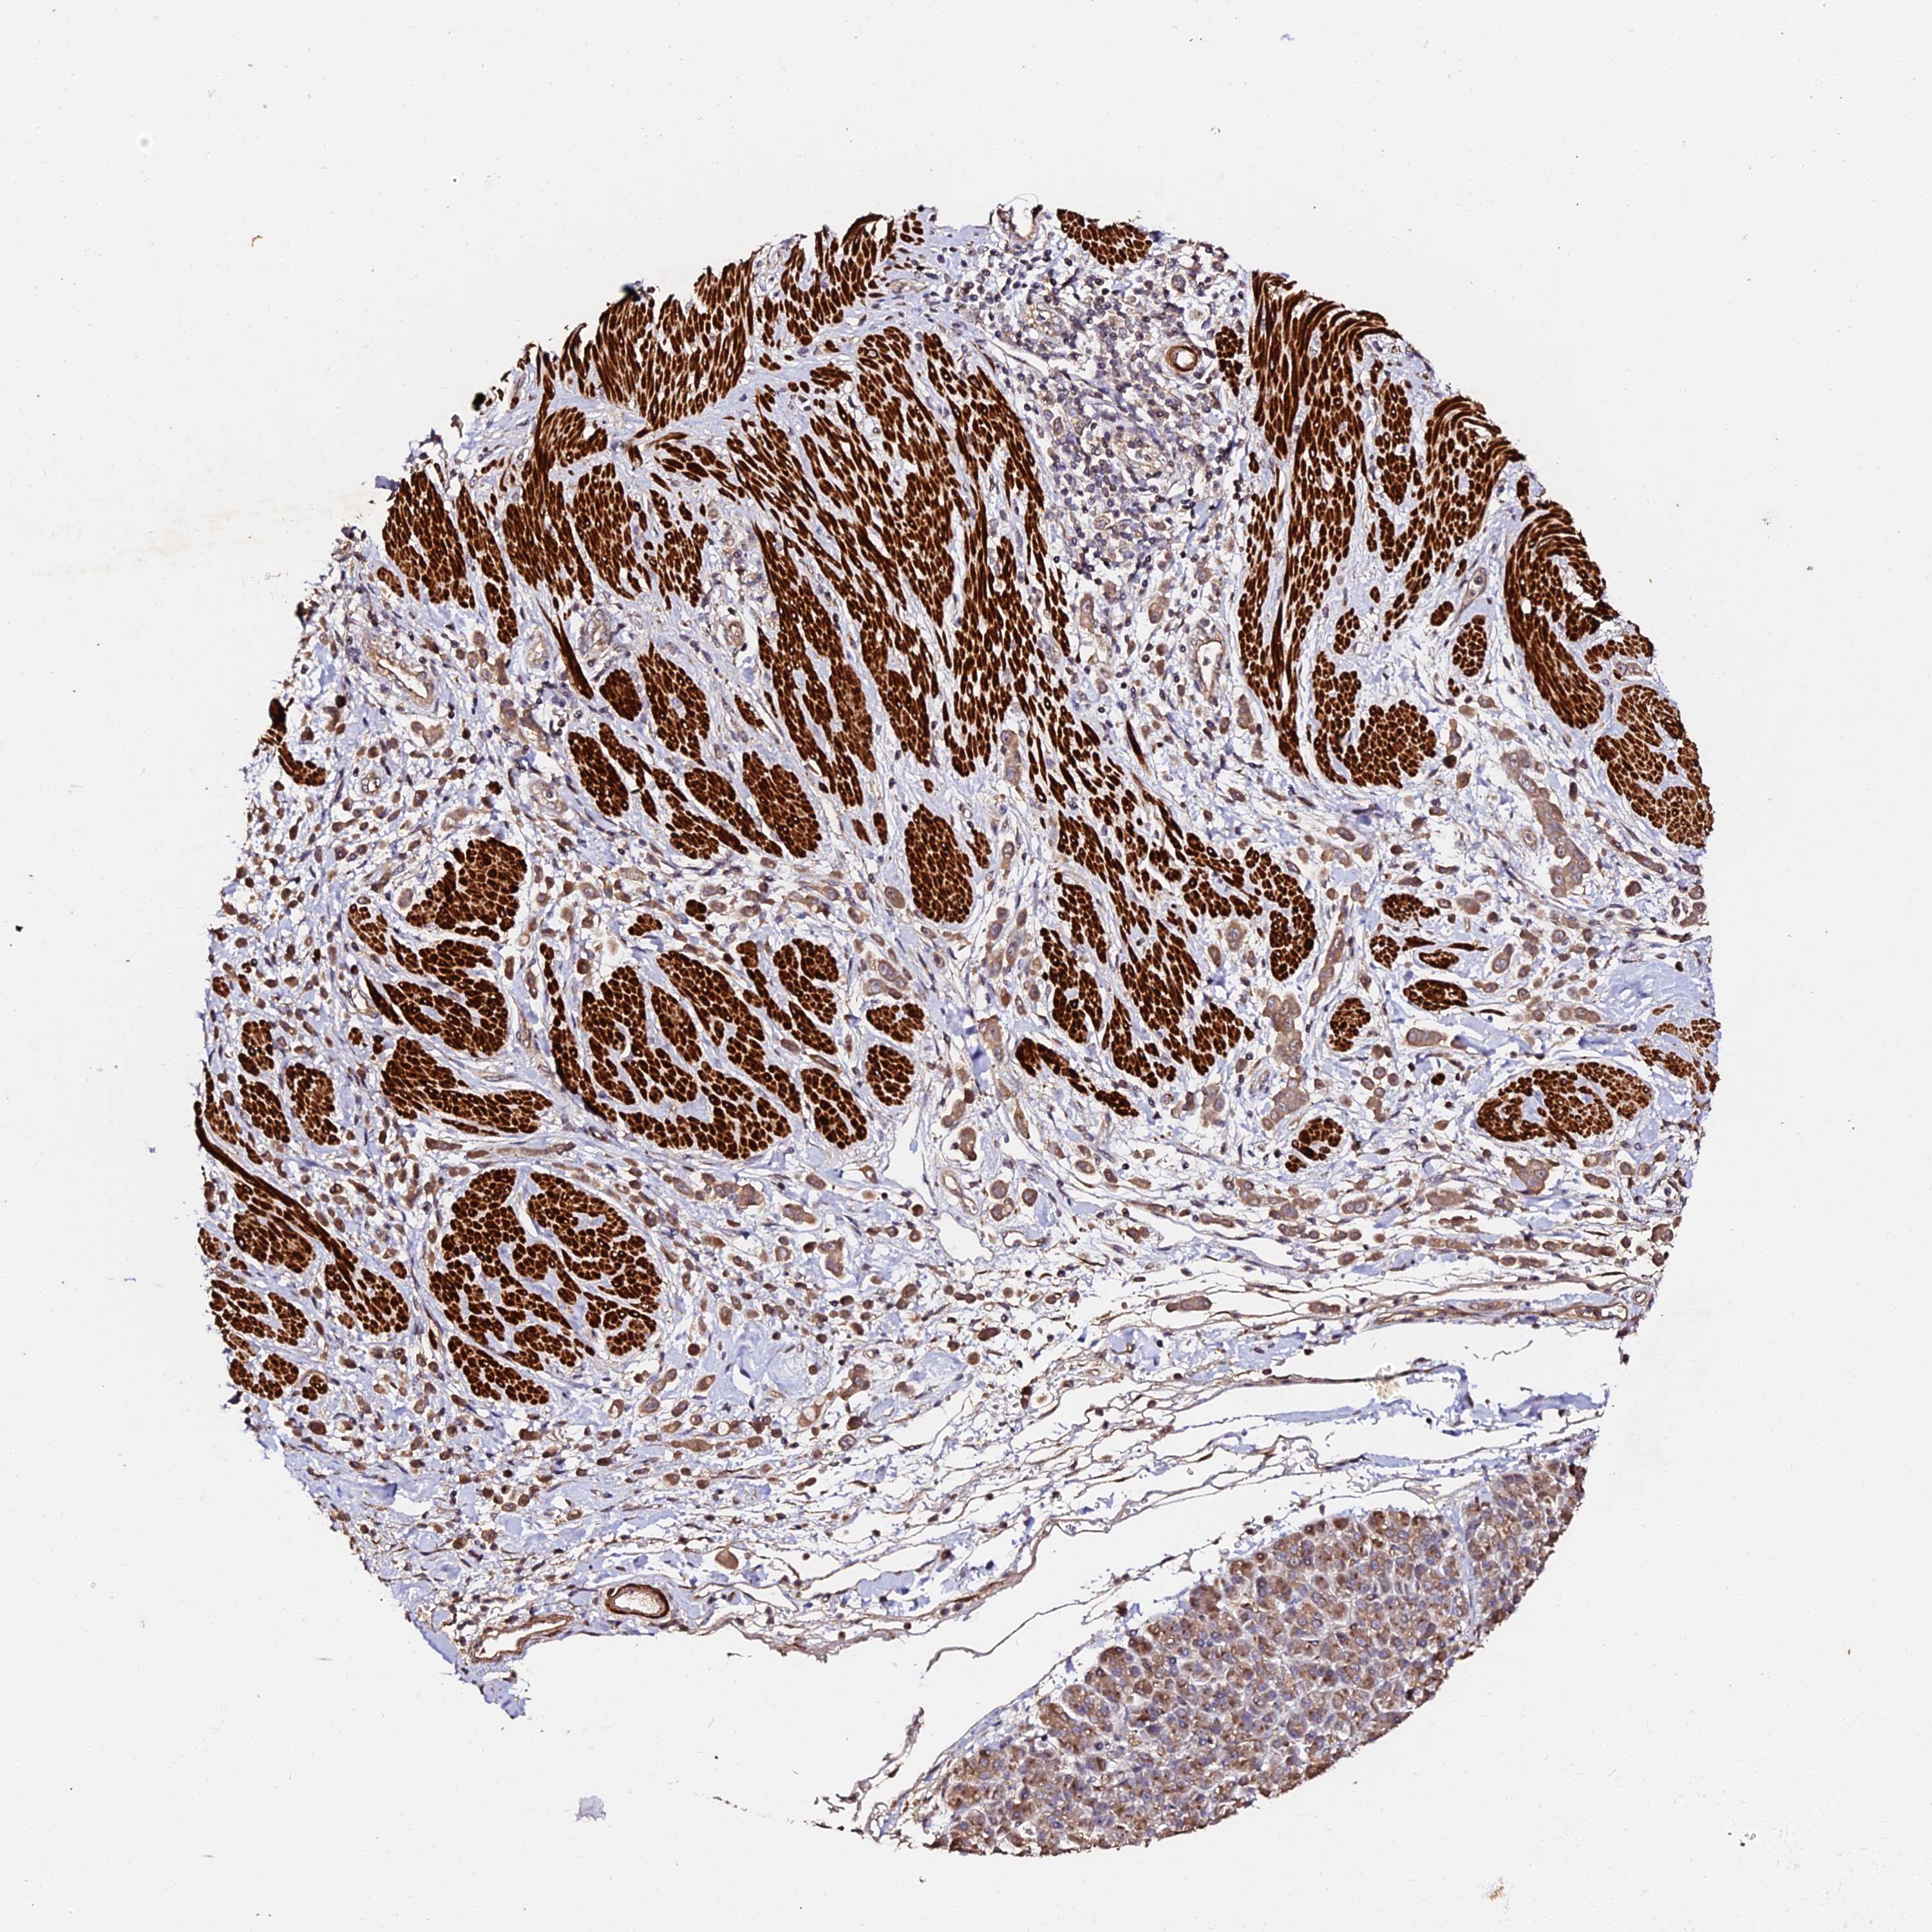

PANCREATIC CANCER - Protein expressioni

A mouse-over function shows sample information and annotation data. Click on an image to view it in a full screen mode. Samples can be filtered based on level of antibody staining by selecting one or several of the following categories: high, medium, low and not detected. The assay and annotation is described here.

Note that samples used for immunohistochemistry by the Human Protein Atlas do not correspond to samples in the TCGA dataset.

Antibody stainingi

Antibody staining in the annotated cell types in the current human tissue is reported as not detected, low, medium, or high, based on conventional immunohistochemistry profiling in selected tissues. This score is based on the combination of the staining intensity and fraction of stained cells.

Each image is clickable and will lead to virtual microscopy that enables deeper exploration of all samples and also displays staining intensity scores, fraction scores and subcellular localization as well as patient and tissue information for each sample.

Antibody HPA039611

Staining

High

Medium

Low

Not detected

Intensity

Strong

Moderate

Weak

Negative

Quantity

>75%

75%-25%

<25%

None

Location

Nuclear

Cytoplasmic/membranous

Cytoplasmic/membranous,nuclear

Adenocarcinoma, NOS